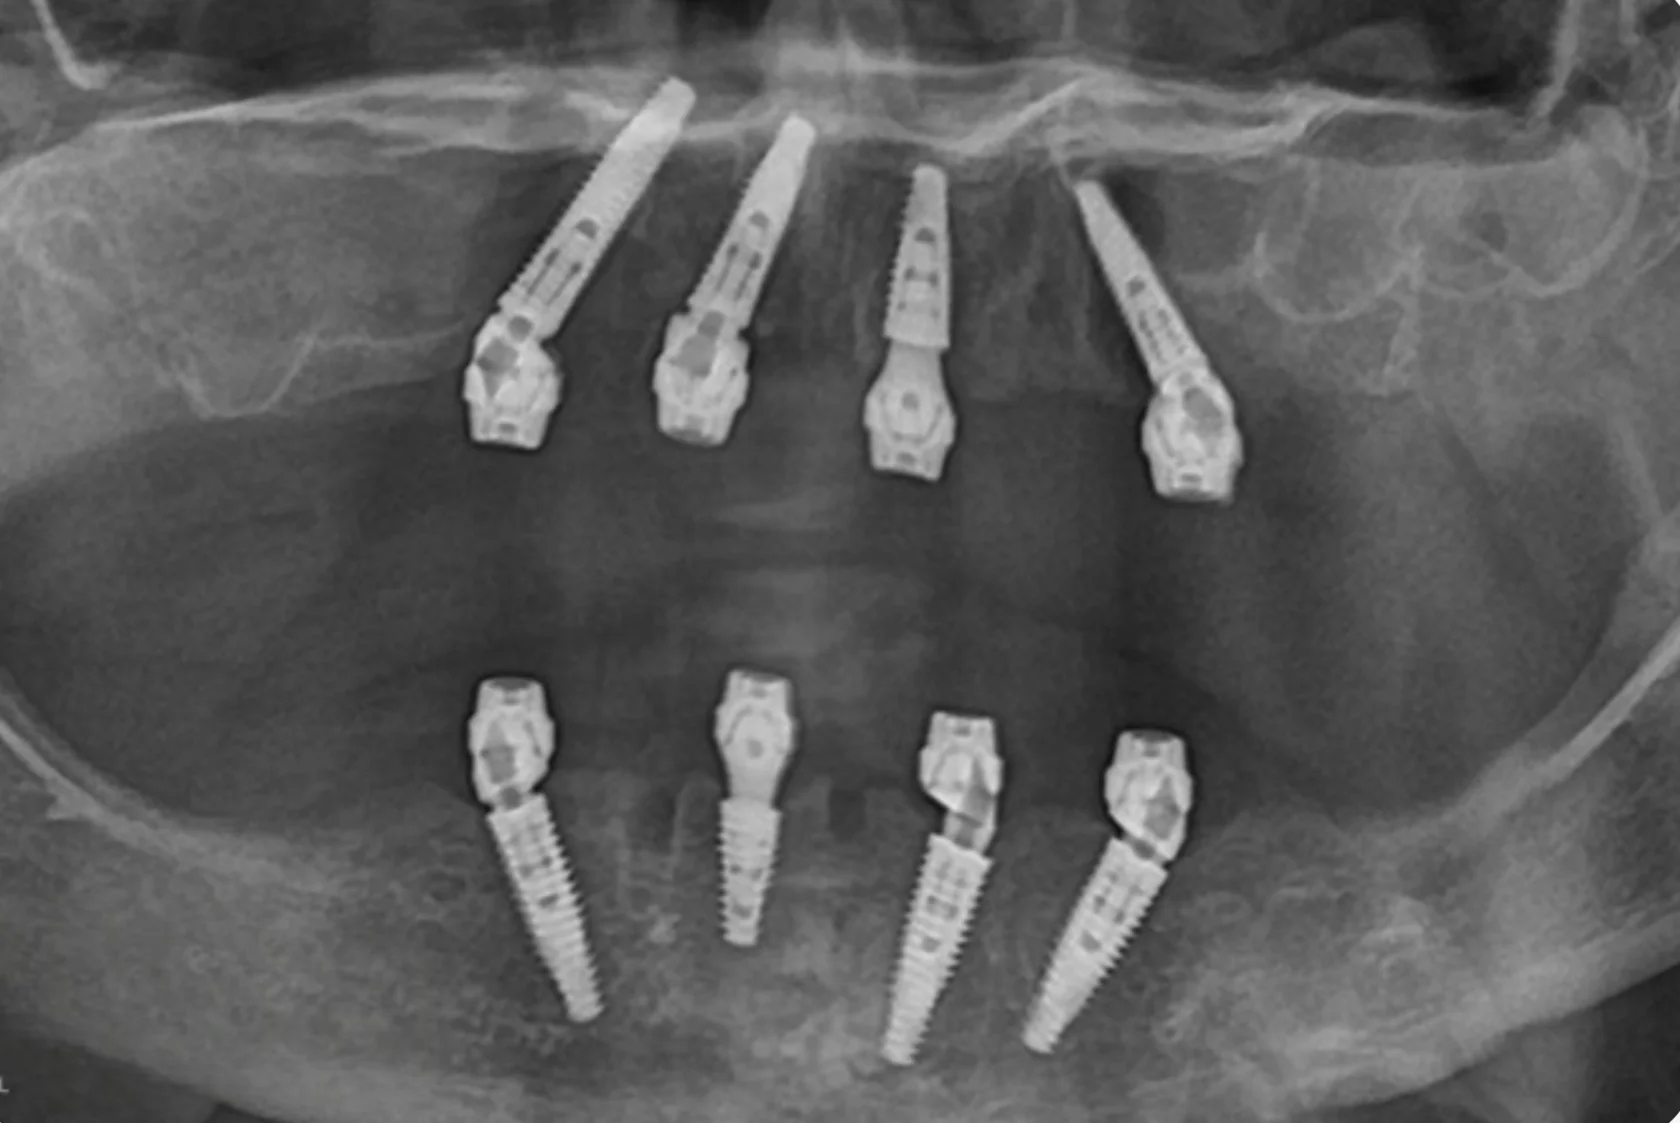

Пациент долго откладывал лечение, сомневаясь в необходимости серьёзного вмешательства и опасаясь сложной операции. Но со временем неудобства и ограничения в повседневной жизни, особенно во время приёма пищи, стали перевешивать сомнения.

На консультации мы подробно разобрали все этапы лечения, обсудили возможные риски и подобрали понятный и комфортный план. В итоге была проведена реабилитация верхней и нижней челюсти по концепции All-on-6 с немедленной нагрузкой. В день операции установлены имплантаты и несъёмные конструкции.

Сегодня пациент признаётся, что зря так долго сомневался — результат превзошёл его ожидания.